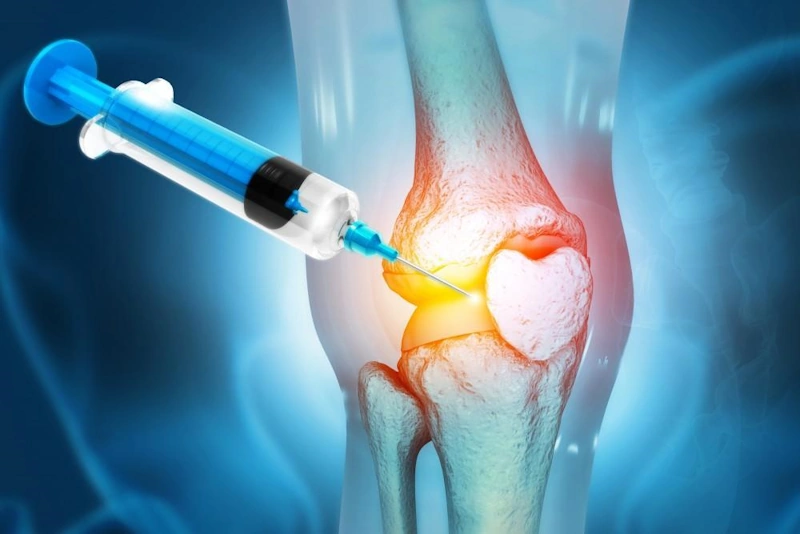

- الحقن في المنطقة المستهدفة: بعد التحضير، تُحقن البلازما في مناطق مثل جلد الوجه أو الرأس أو المناطق الأخرى التي تحتاج إلى ترميم.

- علاج إصابات العضلات والمفاصل: يُستخدم بشكل خاص في مجال جراحة العظام لعلاج الالتهابات وتخفيف آلام المفاصل والأوتار.